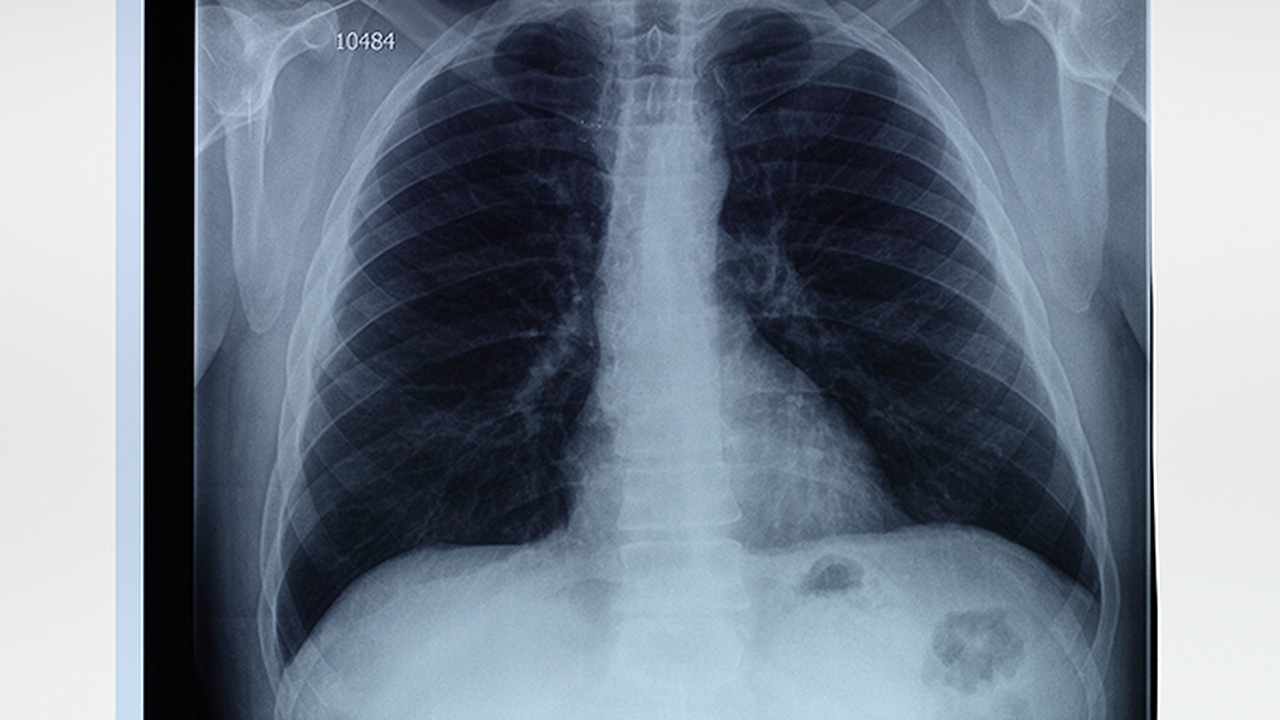

肺部疾病种类繁多,包括肺炎、慢性阻塞性肺病、肺癌等,发病原因涉及感染、环境污染、遗传因素等。及时选择专业医院就诊对疾病控制至关重要。